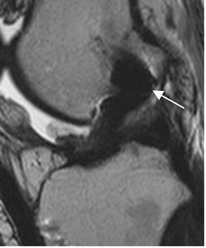

Fig 137. Señal PostQx del injerto normal.

A: RM sagital en T2. Injerto con señal intermedia normal, entre los 4 y 8 meses de evolución.

B: RM sagital en T2. Doble injerto hipointenso normal, de mas de 1 año de evolución.

Fig 138. Cambios PostQx en tendón patelar.

A: RM axial en STIR. Defecto en la parte anterior de la patela, lugar donde se obtuvo el injerto.

B: RM sagital en T2. Cambios reparativos en la parte distal del tendón patelar.